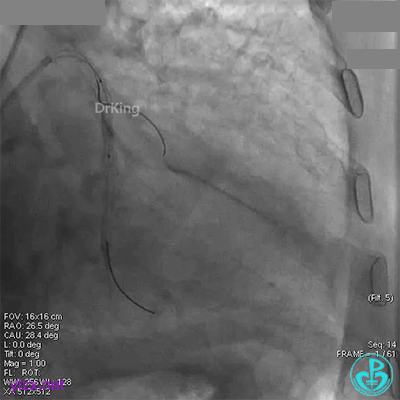

回旋支中段植入2.75×33mm支架后造影,前向血流中断,患者开始出现胸痛。

闭塞段植入2.75×33mm支架后前向血流中断,要排除无复流和支架两端夹层。

近端串联植入3.5×23mm支架后造影,前向血流没有恢复,患者感胸痛明显。